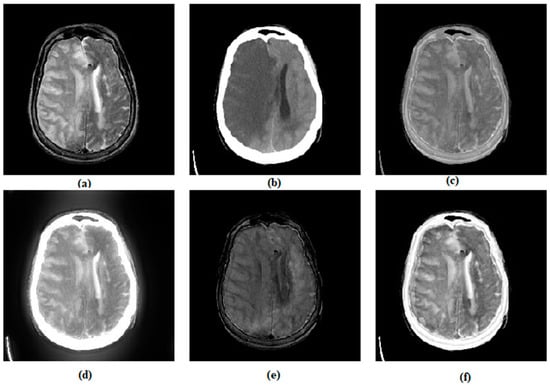

3.1. Subjective Assessment